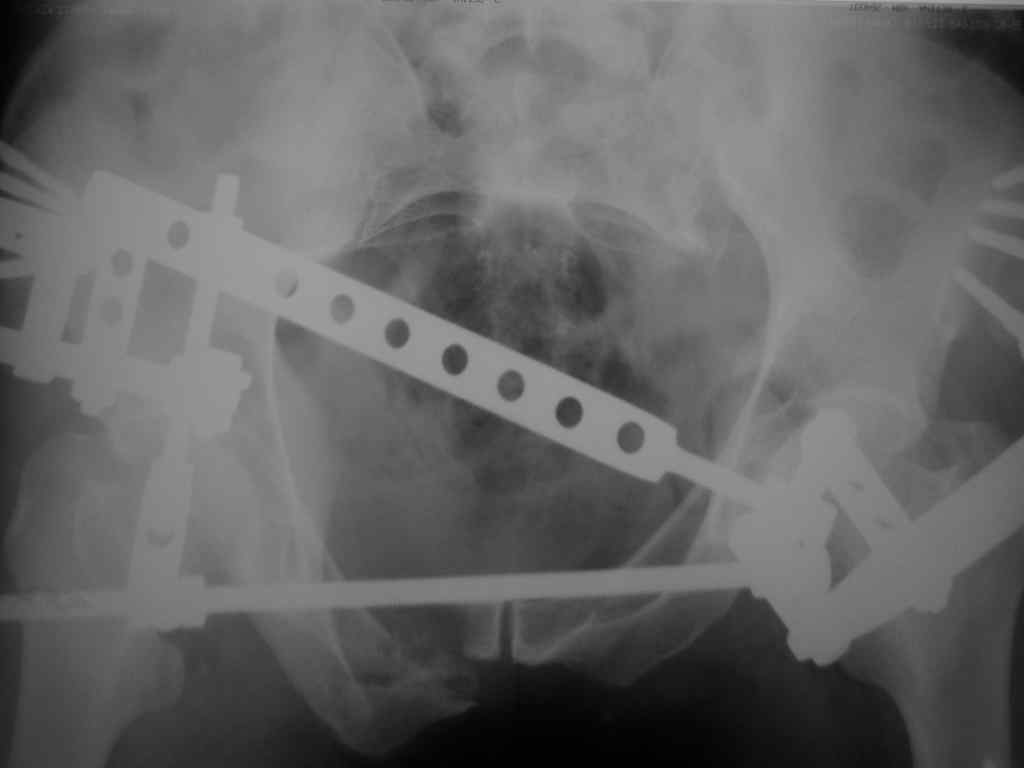

Можно посмотреть на нынешние снимки таза в аппарате, фас и inlet?

Отправитель: Владимир Бахарев 16 Ноябрь 2006, 12:13

Александр Николаевич! Походу самим не справиться (может к себе возмете, а?) Мы бы съездили к вам посмотрели как это делается!

Снимки вот

> (перелом лонной, седалищной костей справа . Разрыв КПС слева)

может быть и двустороннее повреждение задних отделов

по представленным рентгенограммам понять почти ничего невозможно из-за низкого качества, снимки идут в динамике? Для уточнения характера повреждения таза необходимо сделать хотя бы "inlet". повреждение представляется вертикально-нестабильным, в этом случае устранить краниальное и, возможно, передне-заднее смещение "передней рамой" невозможно и дело тут не в жесткости АВФ. Кольцевой опорой можно сделать все что угодно.